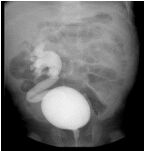

60. 下圖 VCUG 為幾度輸尿管逆流 ? (A) Grade I (B) Grade II (C) Garde III (D) Garde IV (E) Grade V